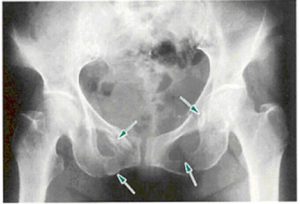

ストラドル骨折(straddle骨折)とは、「恥骨(ちこつ)と坐骨(ざこつ)を骨折することによって、骨盤輪の連続性が損なわれる」という症状です。

ストラドル骨折(straddle骨折)

マルゲーニュ骨折(Malgaigne骨折)も、骨盤骨折の一種です。骨折によって骨が垂直方向にずれてしまい、骨盤がぐらついた状態となります。

マルゲーニュ骨折(Malgaigne骨折)は、「骨盤複垂直骨折」とも呼ばれます。「骨盤複垂直骨折」とは、骨盤輪を形成している部位が2ヵ所以上骨折することです。複数ヵ所を骨折しているため、骨盤の安定性が損なわれます。

下記のイラストを見てください。骨板輪の2ヵ所にヒビが入っています。このような骨折が「骨盤複垂直骨折」と呼ばれる状態です。